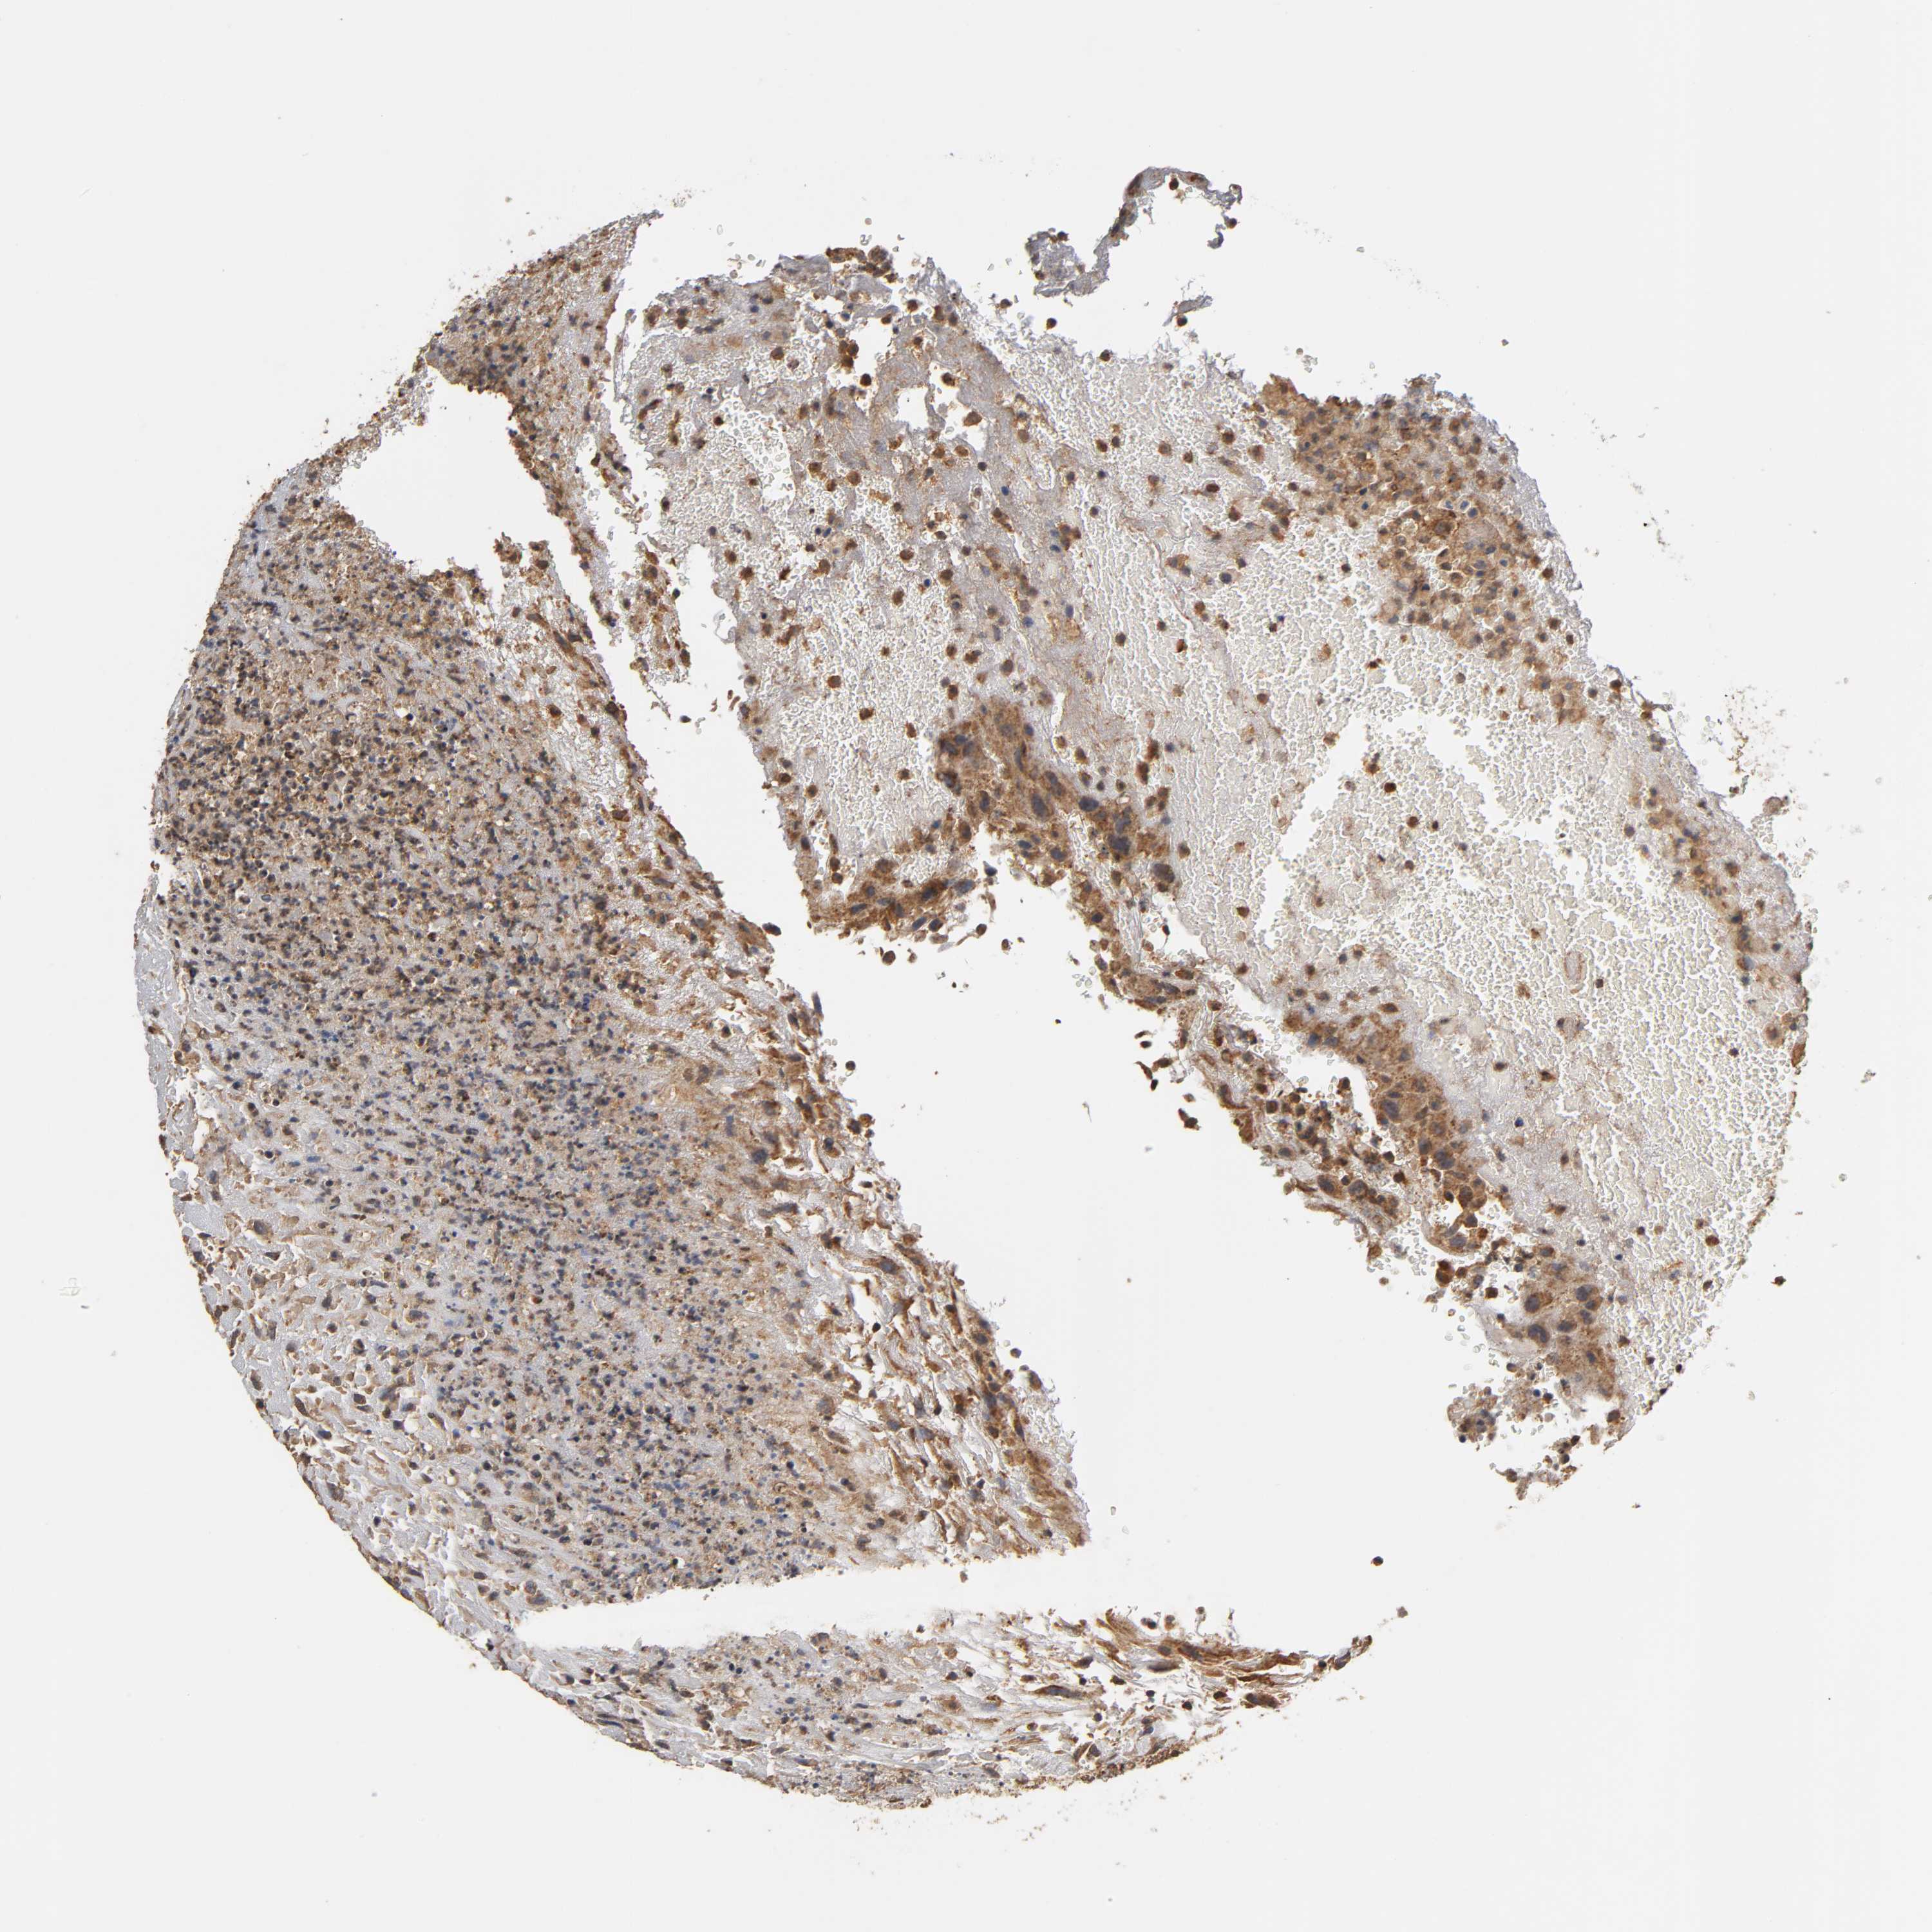

UROTHELIAL CANCER - Protein expressioni

A mouse-over function shows sample information and annotation data. Click on an image to view it in a full screen mode. Samples can be filtered based on level of antibody staining by selecting one or several of the following categories: high, medium, low and not detected. The assay and annotation is described here.

Note that samples used for immunohistochemistry by the Human Protein Atlas do not correspond to samples in the TCGA dataset.

Antibody stainingi

Antibody staining in the annotated cell types in the current human tissue is reported as not detected, low, medium, or high, based on conventional immunohistochemistry profiling in selected tissues. This score is based on the combination of the staining intensity and fraction of stained cells.

Each image is clickable and will lead to virtual microscopy that enables deeper exploration of all samples and also displays staining intensity scores, fraction scores and subcellular localization as well as patient and tissue information for each sample.

Antibody HPA003982

Antibody CAB010278

Staining

High

Medium

Low

Not detected

Intensity

Strong

Moderate

Weak

Negative

Quantity

>75%

75%-25%

<25%

None

Location

Nuclear

Cytoplasmic/membranous

Cytoplasmic/membranous,nuclear

Urothelial carcinoma, High grade

Urothelial carcinoma, Low grade